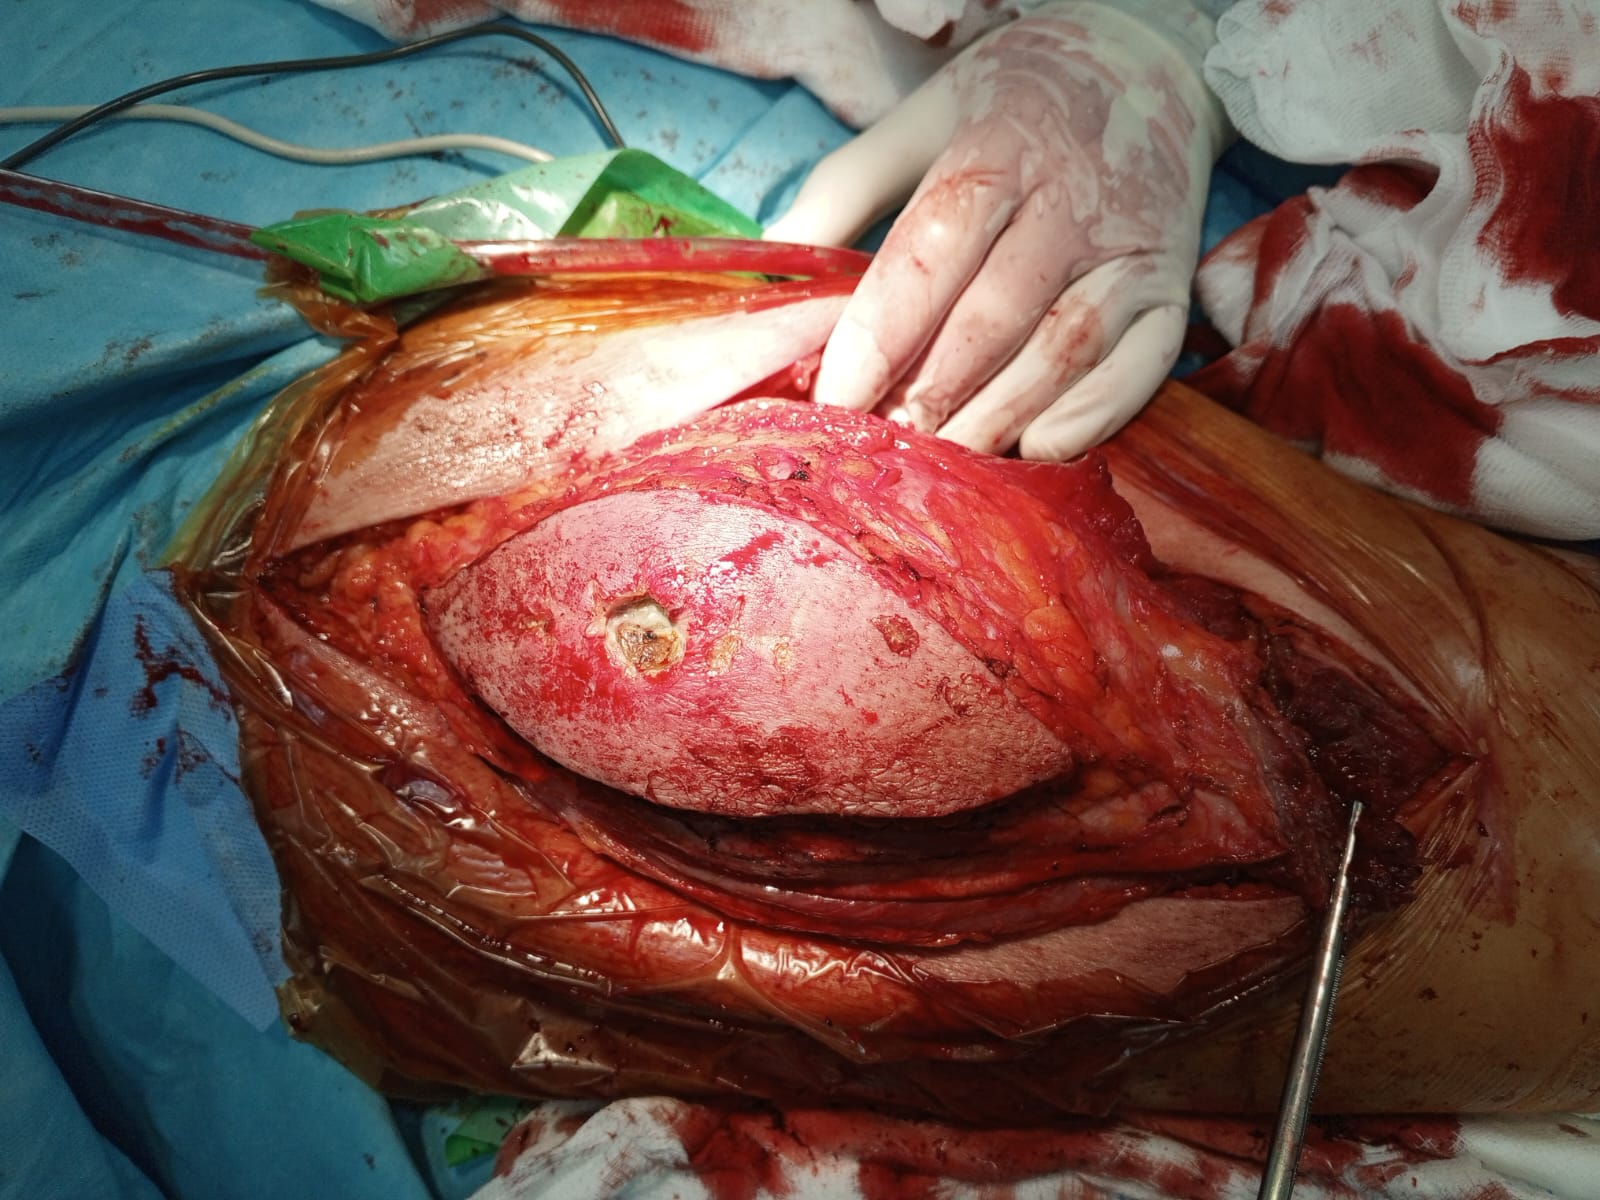

Muscle Cancer